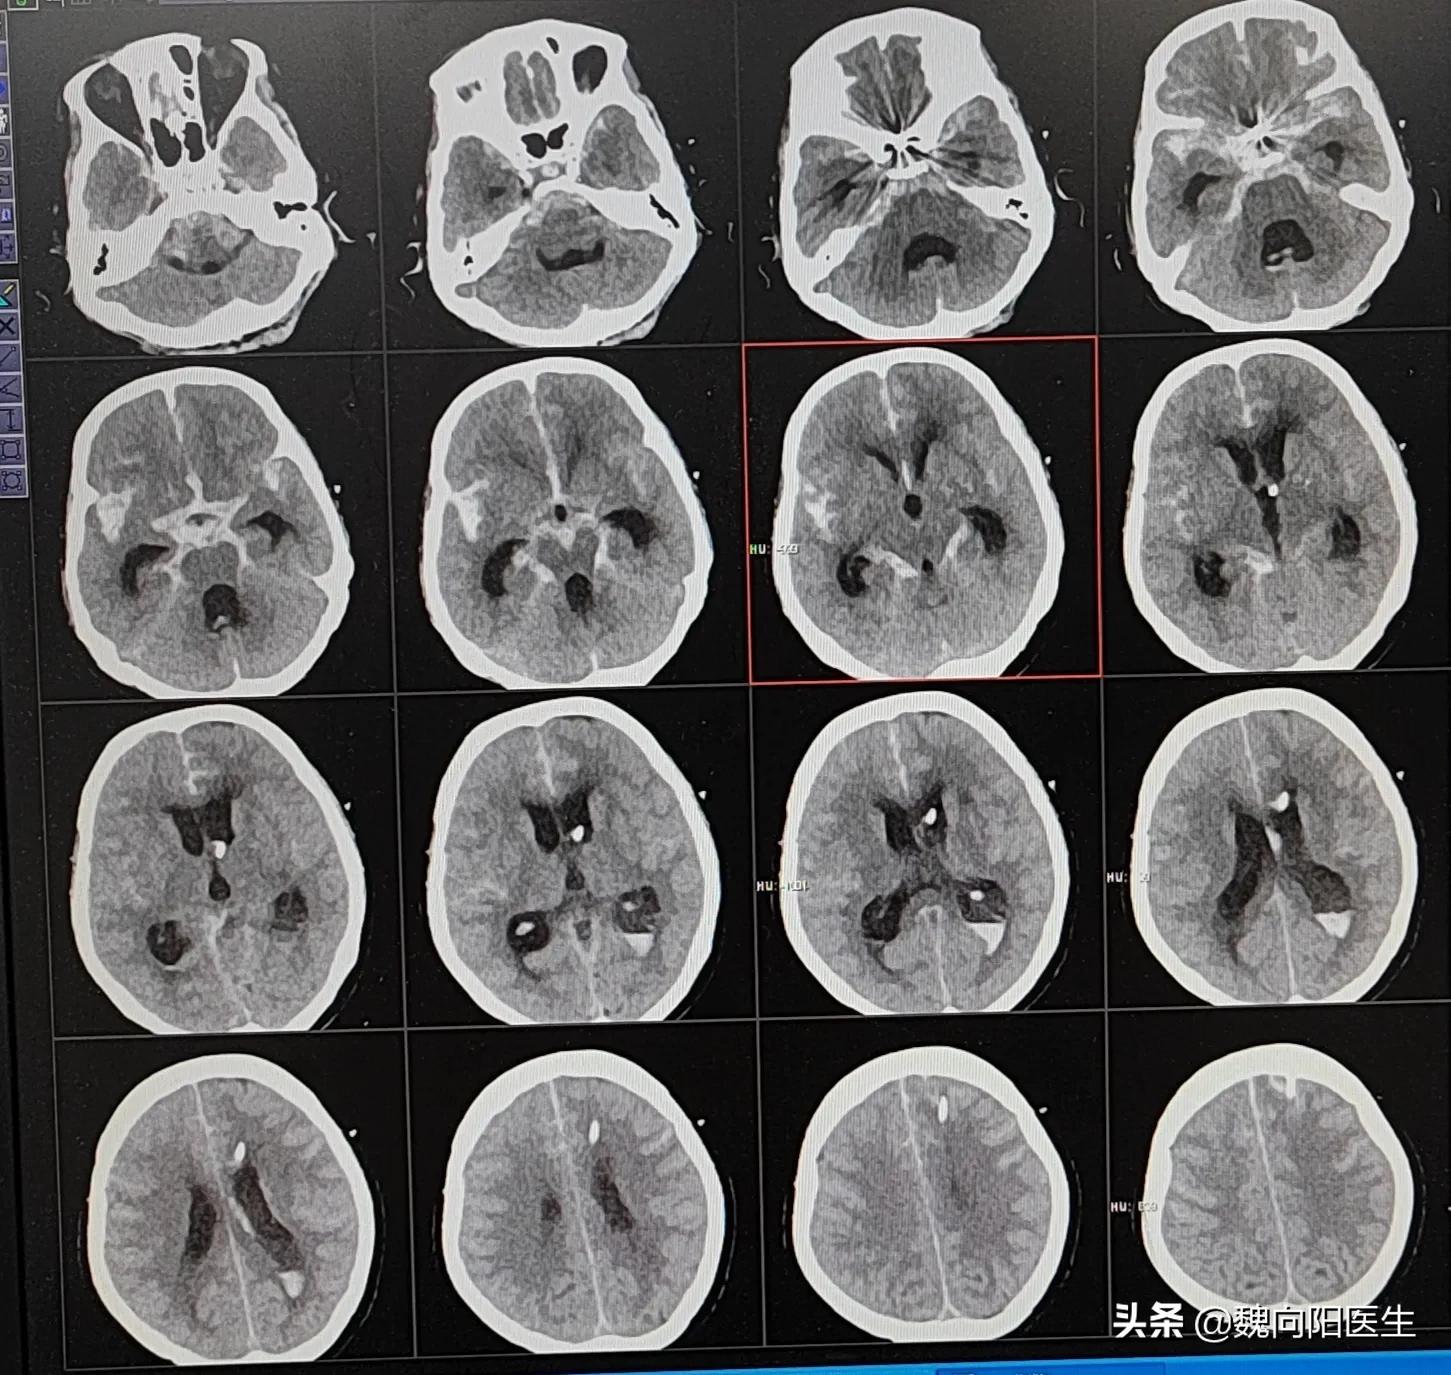

虽说有一部分轻微蛛网膜下腔出血,患者经过积极的治疗之后,把动脉瘤栓塞或夹闭治疗,排除了继续出血的风险,仍然有迟发性脑积水的可能。#脑积水#

迟迟发性脑积水,主要是指发病三个月之后,患者颅内脑脊液重吸收障碍,脑室系统扩大,主要表现为痴呆、步态不稳或大小便障碍。

对于中重度的蛛网膜下腔出血患者死亡率相当高,即使侥幸能够救活,但后期可能会导致严重的残疾,甚至植物人状态。

蛛网膜下腔出血患者死亡率